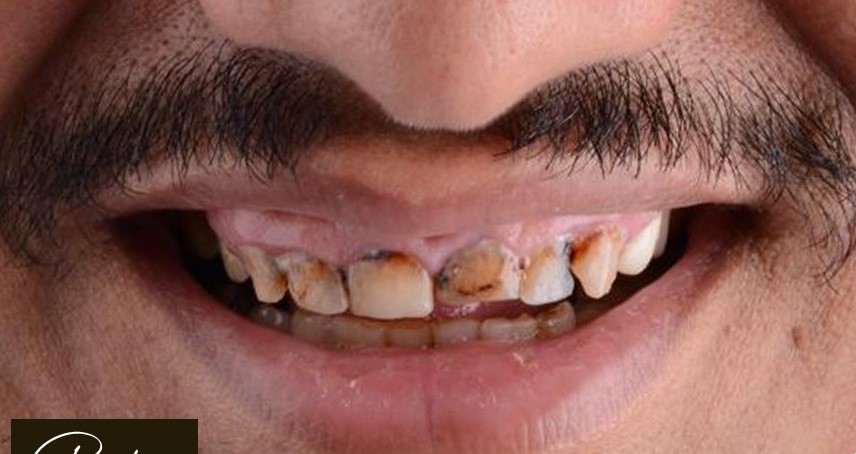

د. حنان ابو الحسن ، مؤسسة Lavender Aesthetic Clinics، هي طبيبة أسنان متخصصة في تركيبات الاسنان ,زراعة الاسنان , حشو عصب ,حشو تجميلي

تميزت برؤيتها اللي بتركز على الجمع بين العلاج الدقيق واللمسة التجميلية، عشان تقدم للمرضى تجربة علاجية مختلفة تجمع بين الصحة، الراحة، والجمال.